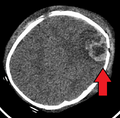

-

An intraparenchymal bleed with overlying skull fracture from abusive head trauma